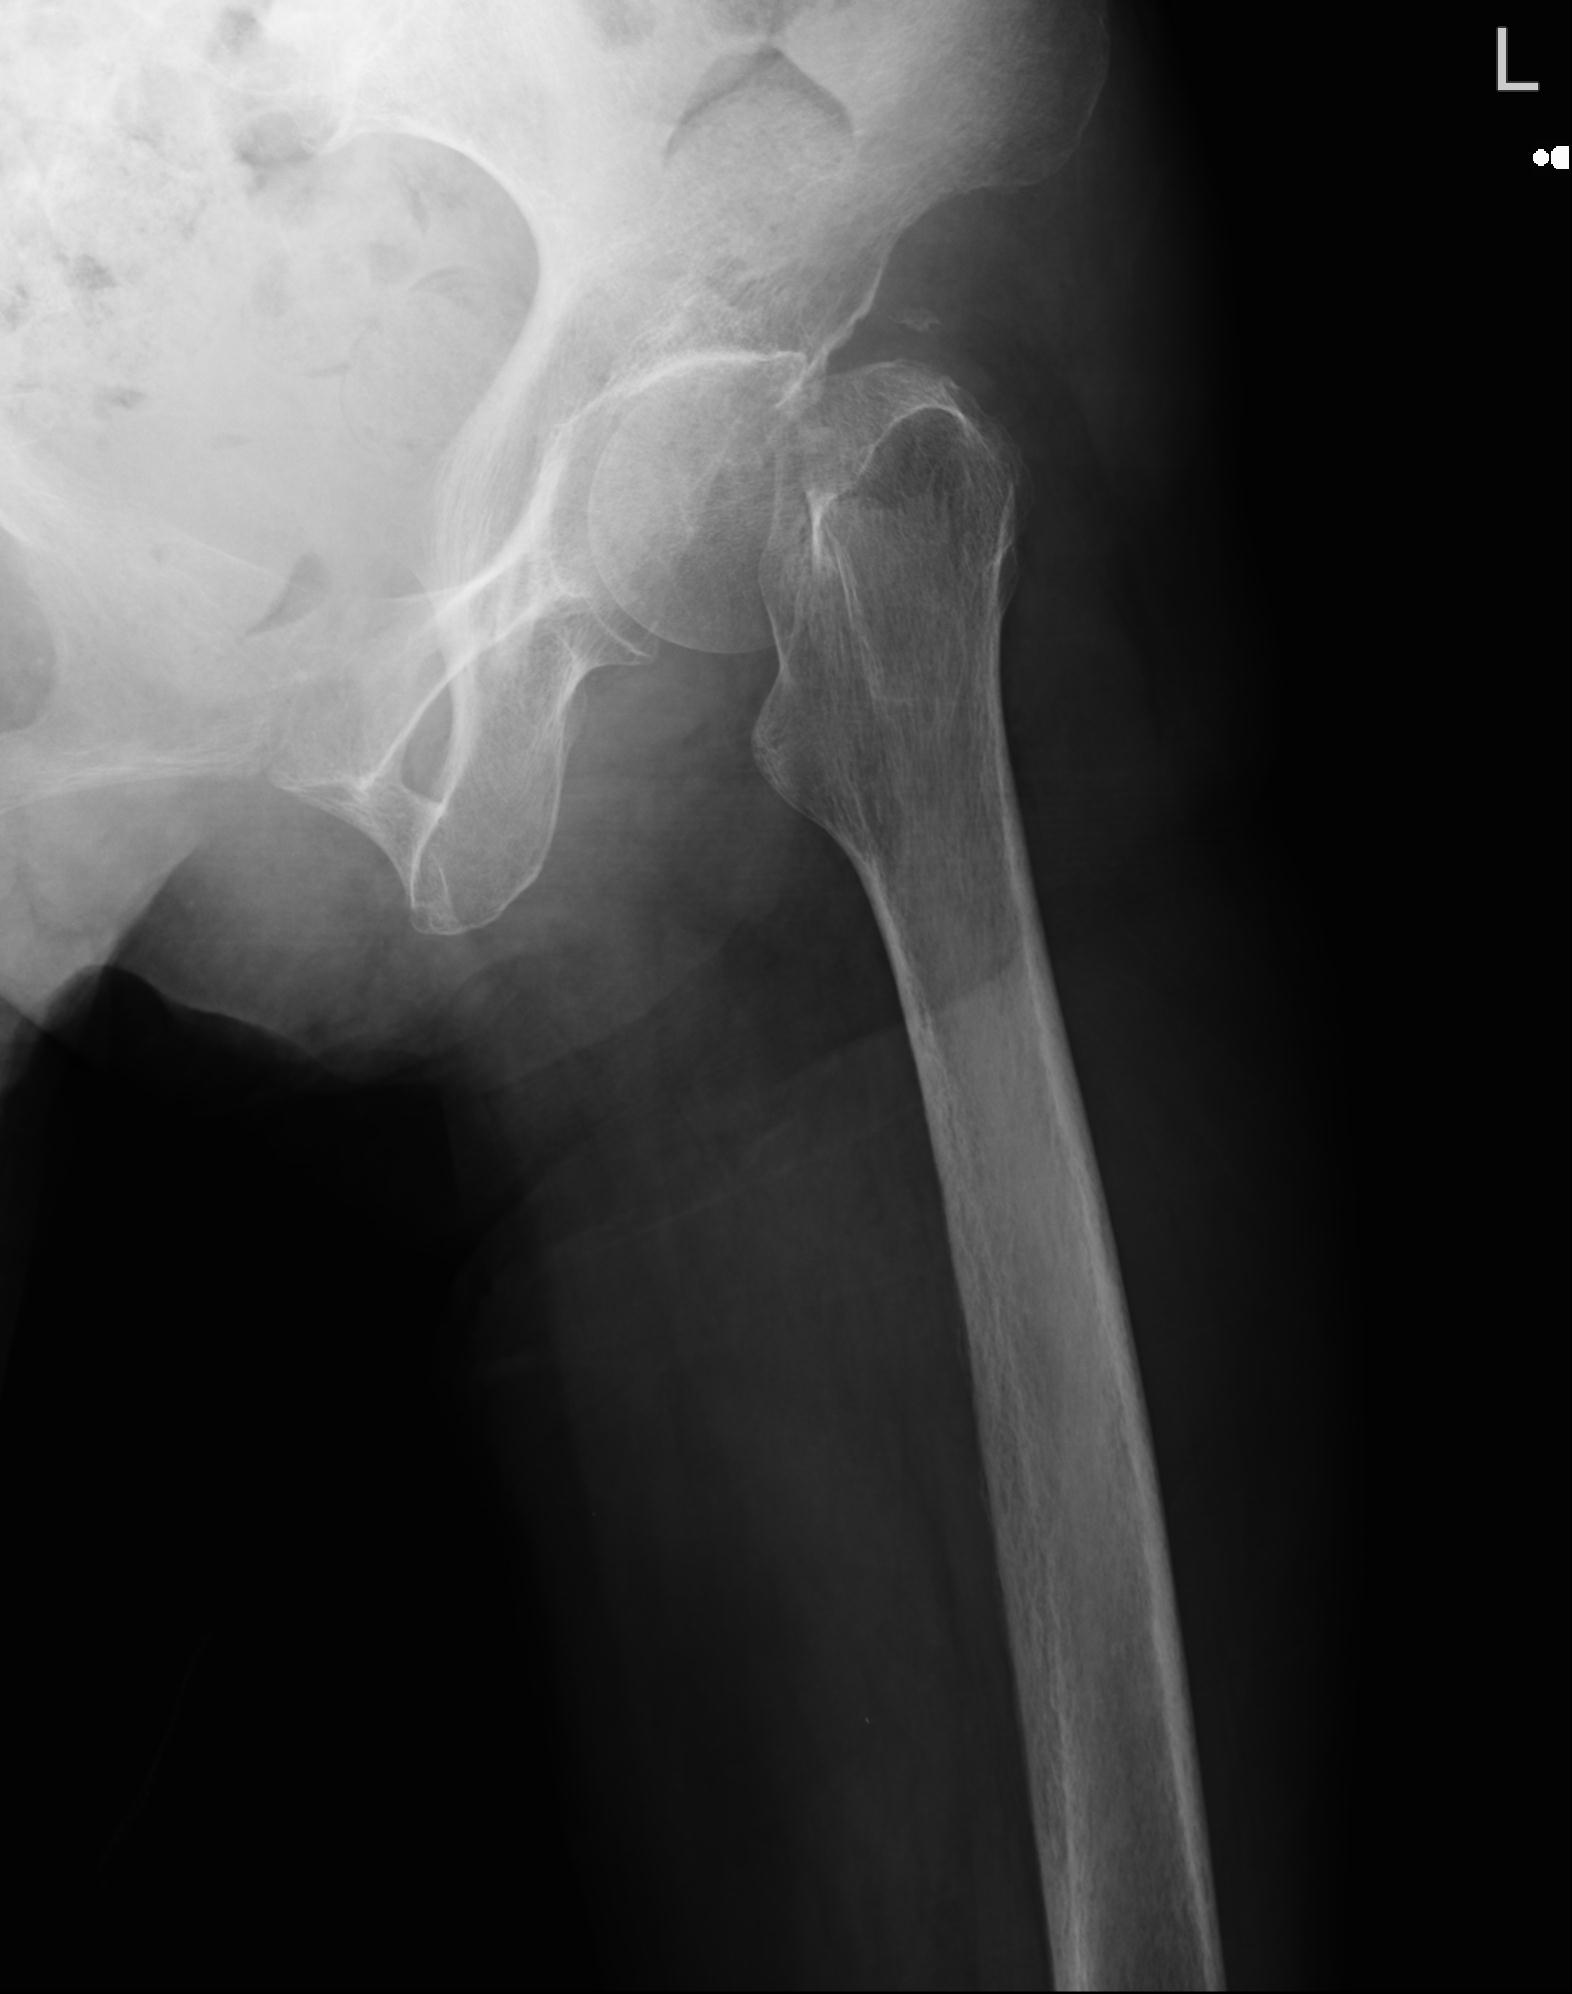

110286 2/17 股関節 2R 74歳女性 右人工骨頭

102903 股関節 2R 1/28 +股関節 2R 1/29 78歳女性 左人工骨頭

46666 1/28 両股正面+軸と 1/26 右手関節 2R 76歳女性 右転子部骨折

37 1/18 両股正面+軸 1/22 2R 86歳女性 右転子下

82084 1/14 1/20 股関節 2R 78歳男性 右人工骨頭

102811 1/13 股関節 2R 1/19 2R 80歳女性 右DHS

91569 3/25 両股正面とラウエン 70歳女性 人工骨頭+バンクーバー